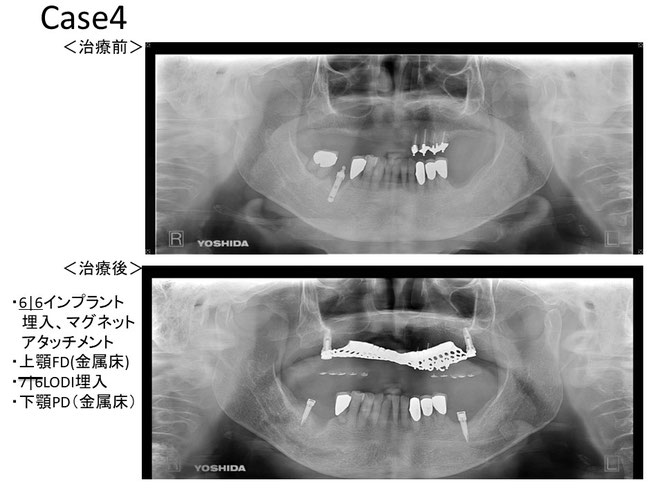

今回のケース

矯正治療後に奥歯の歯ぐきが2~3ミリ退縮。

その結果、露出した根の一部が虫歯になっていました。

治療のポイントは“順番”

このような場合、

✔ 虫歯の除去

✔ 歯ぐきの再生治療

を組み合わせて行います。

治療後の変化

再生治療により、

2~3ミリ下がっていた歯ぐきが回復。

歯の長さが自然なバランスに戻り、

厚みのある丈夫な歯ぐきが再建されました。

奥歯6本の再生治療を行ったケースでは、

虫歯予防という機能面の改善も期待できます。